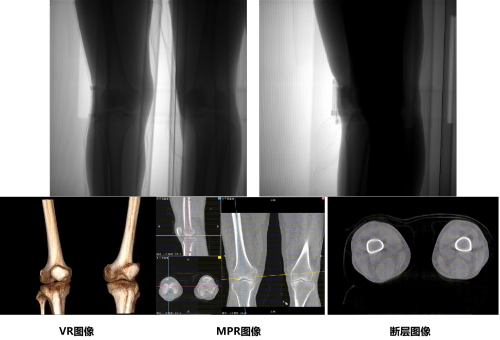

通过安健科技CBCT-DR 珠穆可以完成负重位状态下的三维扫描与重建,能够更丰富的呈现受检者膝关节受力改变状态,可完成断层图像重建、MPR多平面重建以及VR体绘制,给临床提供更多的影像学信息;同时相较于普通平片下的负重位拍摄,负重位动态三维影像重建技术能够避免二维状态下的组织结构重叠、密度分辨率不足、组织解剖结构难以分辨等问题,极大的降低了二维负重位检查带来的漏诊率。